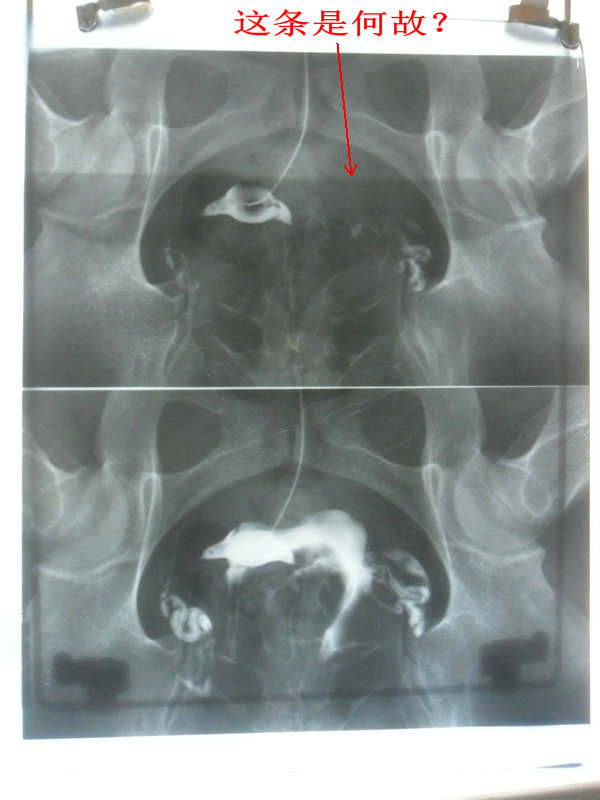

点全片正常;点上下分片第1张有明显的边沿整齐的影条;点左右分片时2张都有;点4分片时4张都有。

上下2分片时:

上下2分片.JPG

左右2分片时:

左右2分片.JPG

上下分片时的胶片:

上下分片1_副本.JPG

上下分片2_副本.JPG